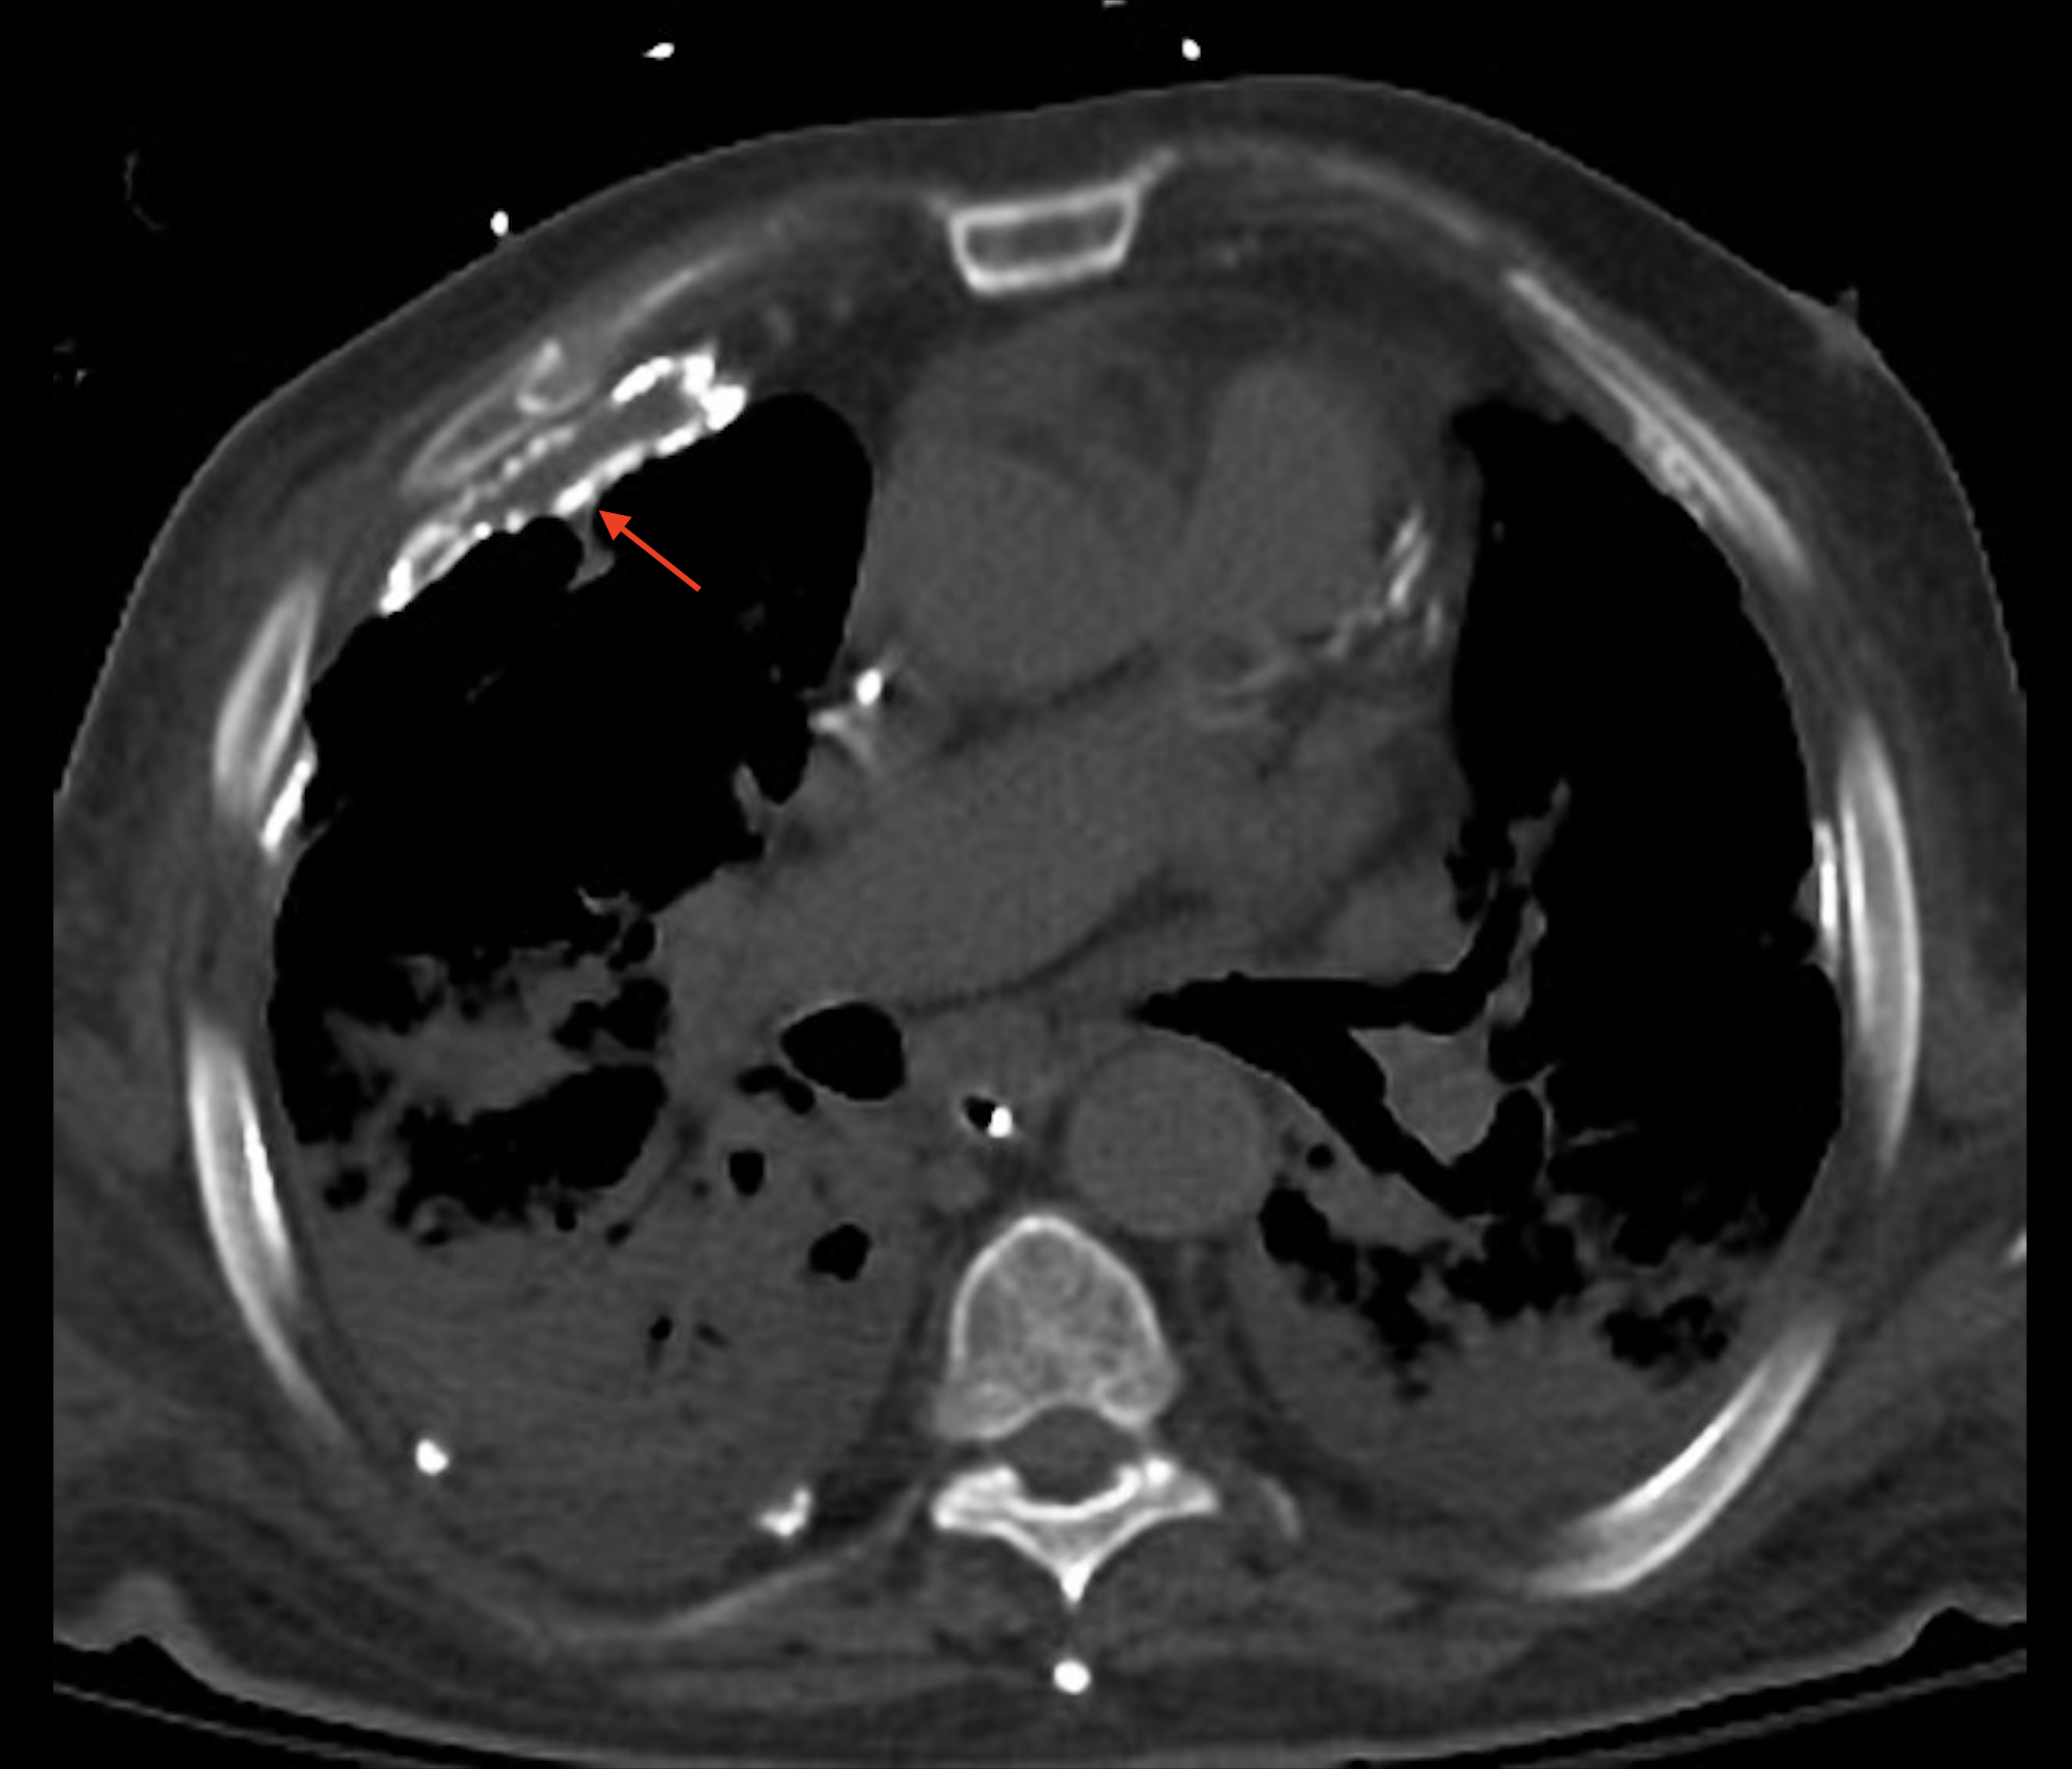

On reconnaît les plaques pleurales facilement lorsqu’elles sont multiples, volumineuse et calcifiée. À un stade précoce il faut attentivement analyser les contours de la plèvre périphérique, coupe par coupes dans les deux fenêtres parenchymateuses et médiastinales pour repérer un épaississement très modérée (quelques millimètres), visible sur parfois moins de 1 cm.

• Tomodensitométrie (scanner) : c’est l’examen le plus sensible pour détecter les plaques pleurales. Il permet une évaluation détaillée de leur taille, de leur distribution et de leur caractère calcifié. Les plaques apparaissent comme des épaississements de la plèvre avec une densité tissulaire, et peuvent être mieux visualisées grâce à la reconstruction multiplanaire.